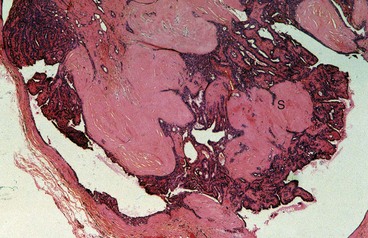

Intraduct papillomas are localised areas of epithelial proliferation. They are villous lesions composed of a fibrovascular core covered by a double layer of epithelium. They usually occur as solitary lesions in the main lactiferous ducts close to the nipple but multiple papillomas can occur more peripherally. Papillomas are not premalignant (see Fig. 45.23). They present as spontaneous blood-stained or clear watery nipple discharge, often from a single duct; a retroareolar mass may be palpable. These lesions are best imaged with ultrasound and the diagnosis confirmed on core biopsy. Papillomas are treated by excision of the affected duct (microdochectomy) or a group of ducts (wedge resection). If the causative lesion cannot be found at operation, a subareolar excision of all the ducts may be necessary.